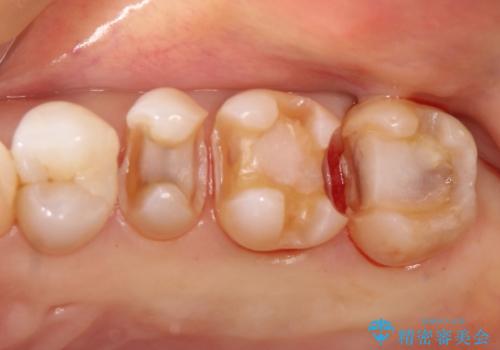

- 昔入れた銀歯のやりかえを主訴に来院されました。

セラミックインレーにて修復を行いました。

歯の強度を高めるためセラミッククラウンの提案もさせていただきましたが、患者様の希望でセラミックインレーにて修復を行なっております。